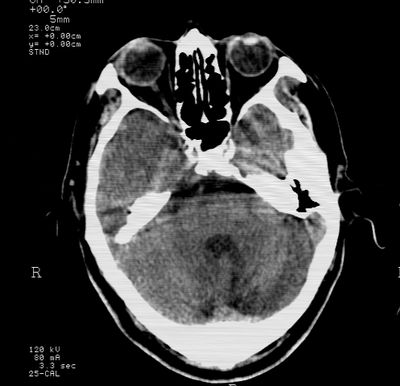

标题: CT21793:李x,男,62岁,头疼,头晕,家属否认有出血病史, [打印本页]

标题: CT21793:李x,男,62岁,头疼,头晕,家属否认有出血病史,

右基底节,海马并侵及右枕,左枕叶梗塞

支持右基底节,海马并侵及右枕,左枕叶梗塞。

支持右基底节,海马并侵及右枕,左枕叶梗塞。建议增强。

支持右基底节,海马并侵及右枕,左枕叶梗塞

多发梗塞,左小脑软化灶

多发性脑梗塞。

考虑多发脑梗塞,建议mri检查。